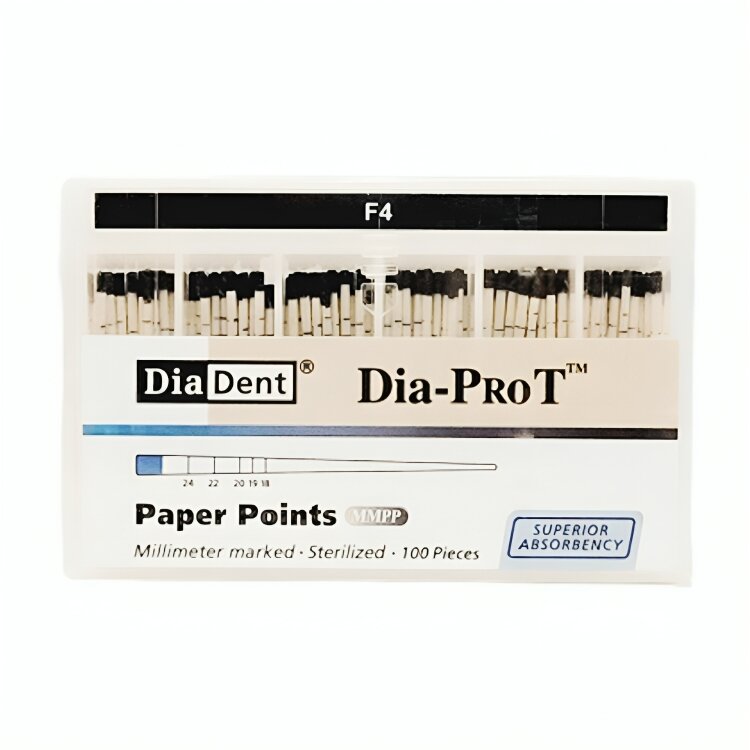

Endodontics: Gutta Percha & Paper Points.